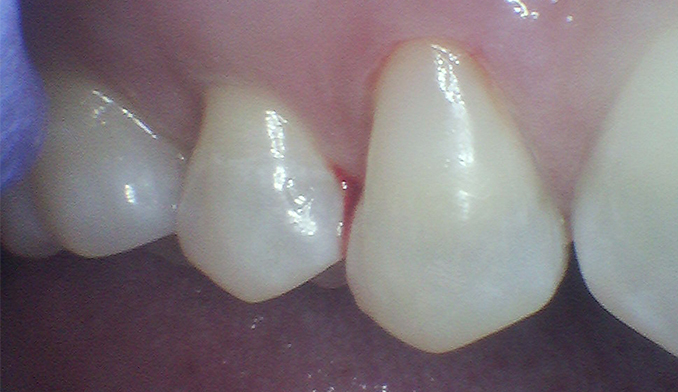

Front Tooth Repair with Bonding

The patient fractured her front tooth. We restored both the appearance and function of the tooth using cosmetic bonding, achieving a natural-looking and durable result.